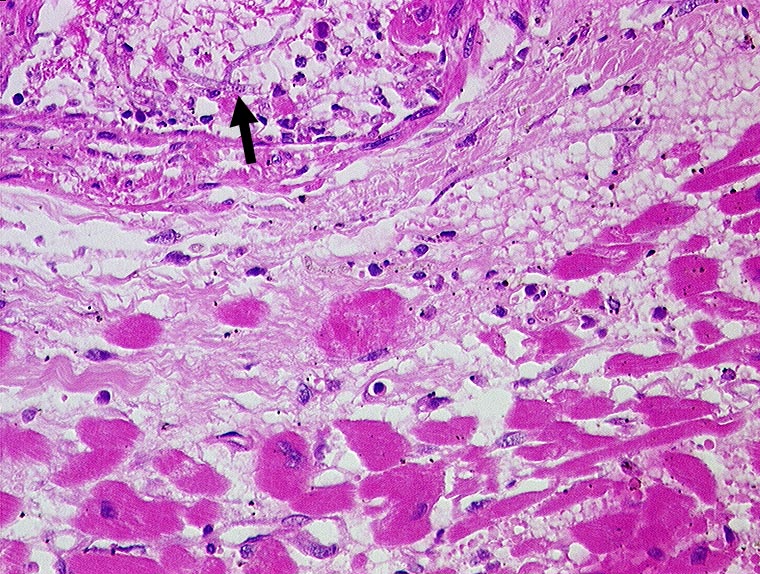

Aspergillussepsis mit Myokardbefall

► Aspergillushyphen in einem intramyokardialen Gefäss.

Aspergillussepsis. Chronische lymphatische Leukämie. Metastasierendes Spinaliom.

Histologie